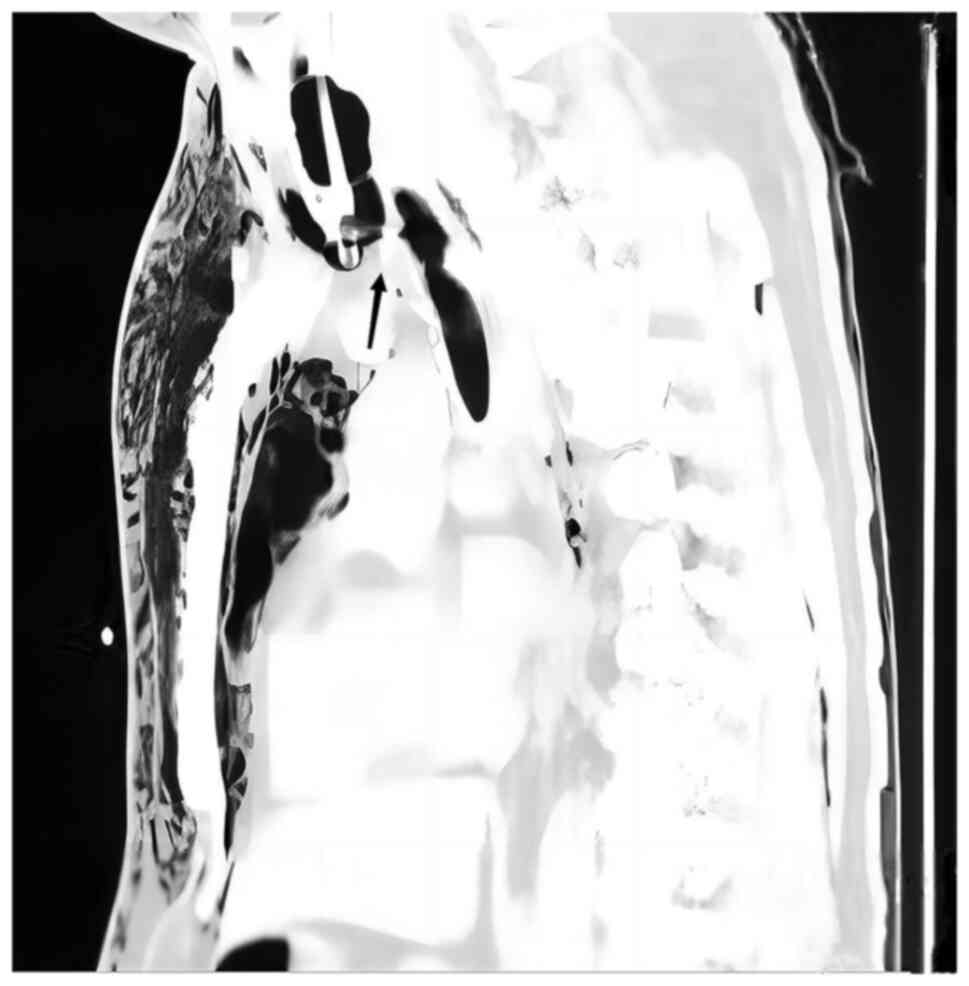

Figure 1

CT scan images of the patient's chest upon hospital admission (sagittal view). The black arrow indicates complete rupture of the main trachea.

A 39-year-old man was crushed by an excavator during the course of his work in July 2022. The patient experienced severe chest pain immediately after the injury, as well as chest tightness and shortness of breath, dyspnea and continuous hemoptysis, without hematemesis. The patient presented to the emergency room of Jiashan First People's Hospital (Jiaxing, China) 30 min after the injury occurred, where they were admitted with clear consciousness and dysphoria, a body temperature of 36.2˚C, heart rate of 112 beats/min (bpm), respiration rate of 38 breaths/min, blood pressure of 107/72 mmHg and oxygen saturation (SPO2) of 92%. Upon examination of the patient, there was swelling and bruising in the neck, massive subcutaneous emphysema on both sides of the chest wall and beneath the abdominal wall, drum sounds on percussion of both lungs and a loss of breath sounds on auscultation. On physical examination, the patient's oxygen saturation had declined to <80%, tracheal intubation was performed immediately and CT was performed. CT examination demonstrated multiple air accumulations in the cerebral sulcus, cerebral fissure and ventricles, collapse of the main bronchus, bronchial occlusion on both sides, pneumothorax on both sides with partial lung tissue inflation, 70% lung compression, multiple rib fractures on both sides, massive subcutaneous emphysema on both sides of the chest wall, fracture of the right scapula and fracture of the right clavicle (Figs. 1 and 2). The results of the blood gas analysis were as follows: Partial pressure of oxygen (PaO2), 51.3 mmHg (normal range: 80-100 mmHg); partial pressure of carbon dioxide, 67.2 mmHg (normal range: 35-45 mmHg); base excess, -8.4 mmol/l (normal range: -3-+3 mmol/l); pH, 7.15 (normal range: 7.35-7.45); lactate level, 4.5 mmol/l (normal range: 0.5-2.2 mmol/l); and hemoglobin level, 104 g/l (normal range: 130-175 g/l).